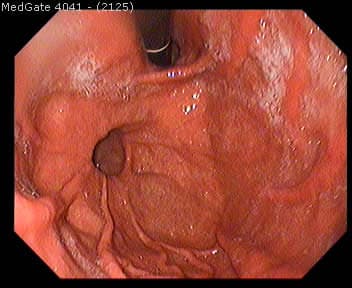

Kalın bağırsak gibi içi boş organlarda organın içini döşeyen tabakanın dış tabakalardaki zayıf noktalardan dışarı keseleşmesi olayına Divertikül denir. Divertikülozis kalın bağırsakta yerleşen birden fazla divertikül için kullanılan bir terimdir. En fazla kalın bağırsakta son kısımlarda (sigmoid ve rektosigmoid) gözlenir. Sıklıkla 30 yaşından önce görülmez ve yaş ilerledikçe görülme sıklığı artar, kadın/erkek oranı farklılık göstermez. Toplumlarda tüketilen gıdaların posa kapsamı azaldıkça görülme sıklığının arttığına inanılır.

Tam mekanizması bilinmemekle birlikte posadan fakir beslenme (lifsiz ile beslenme) ve spastik kolon hastalığı ile yakından ilgilidir. Kalın bağırsak duvarının dış tabakalarını oluşturan adale tabakasını bağırsak duvarını besleyen atar damarların deldikleri noktalardan, iç kısmını döşeyen (mukoza) tabakasının (fıtıklaşması) sonucu meydana gelir. Bu keseleşmelerin atar damarlarla olan komşuluğu nedeniyle Divertikülozis kanamaya neden olabilir.